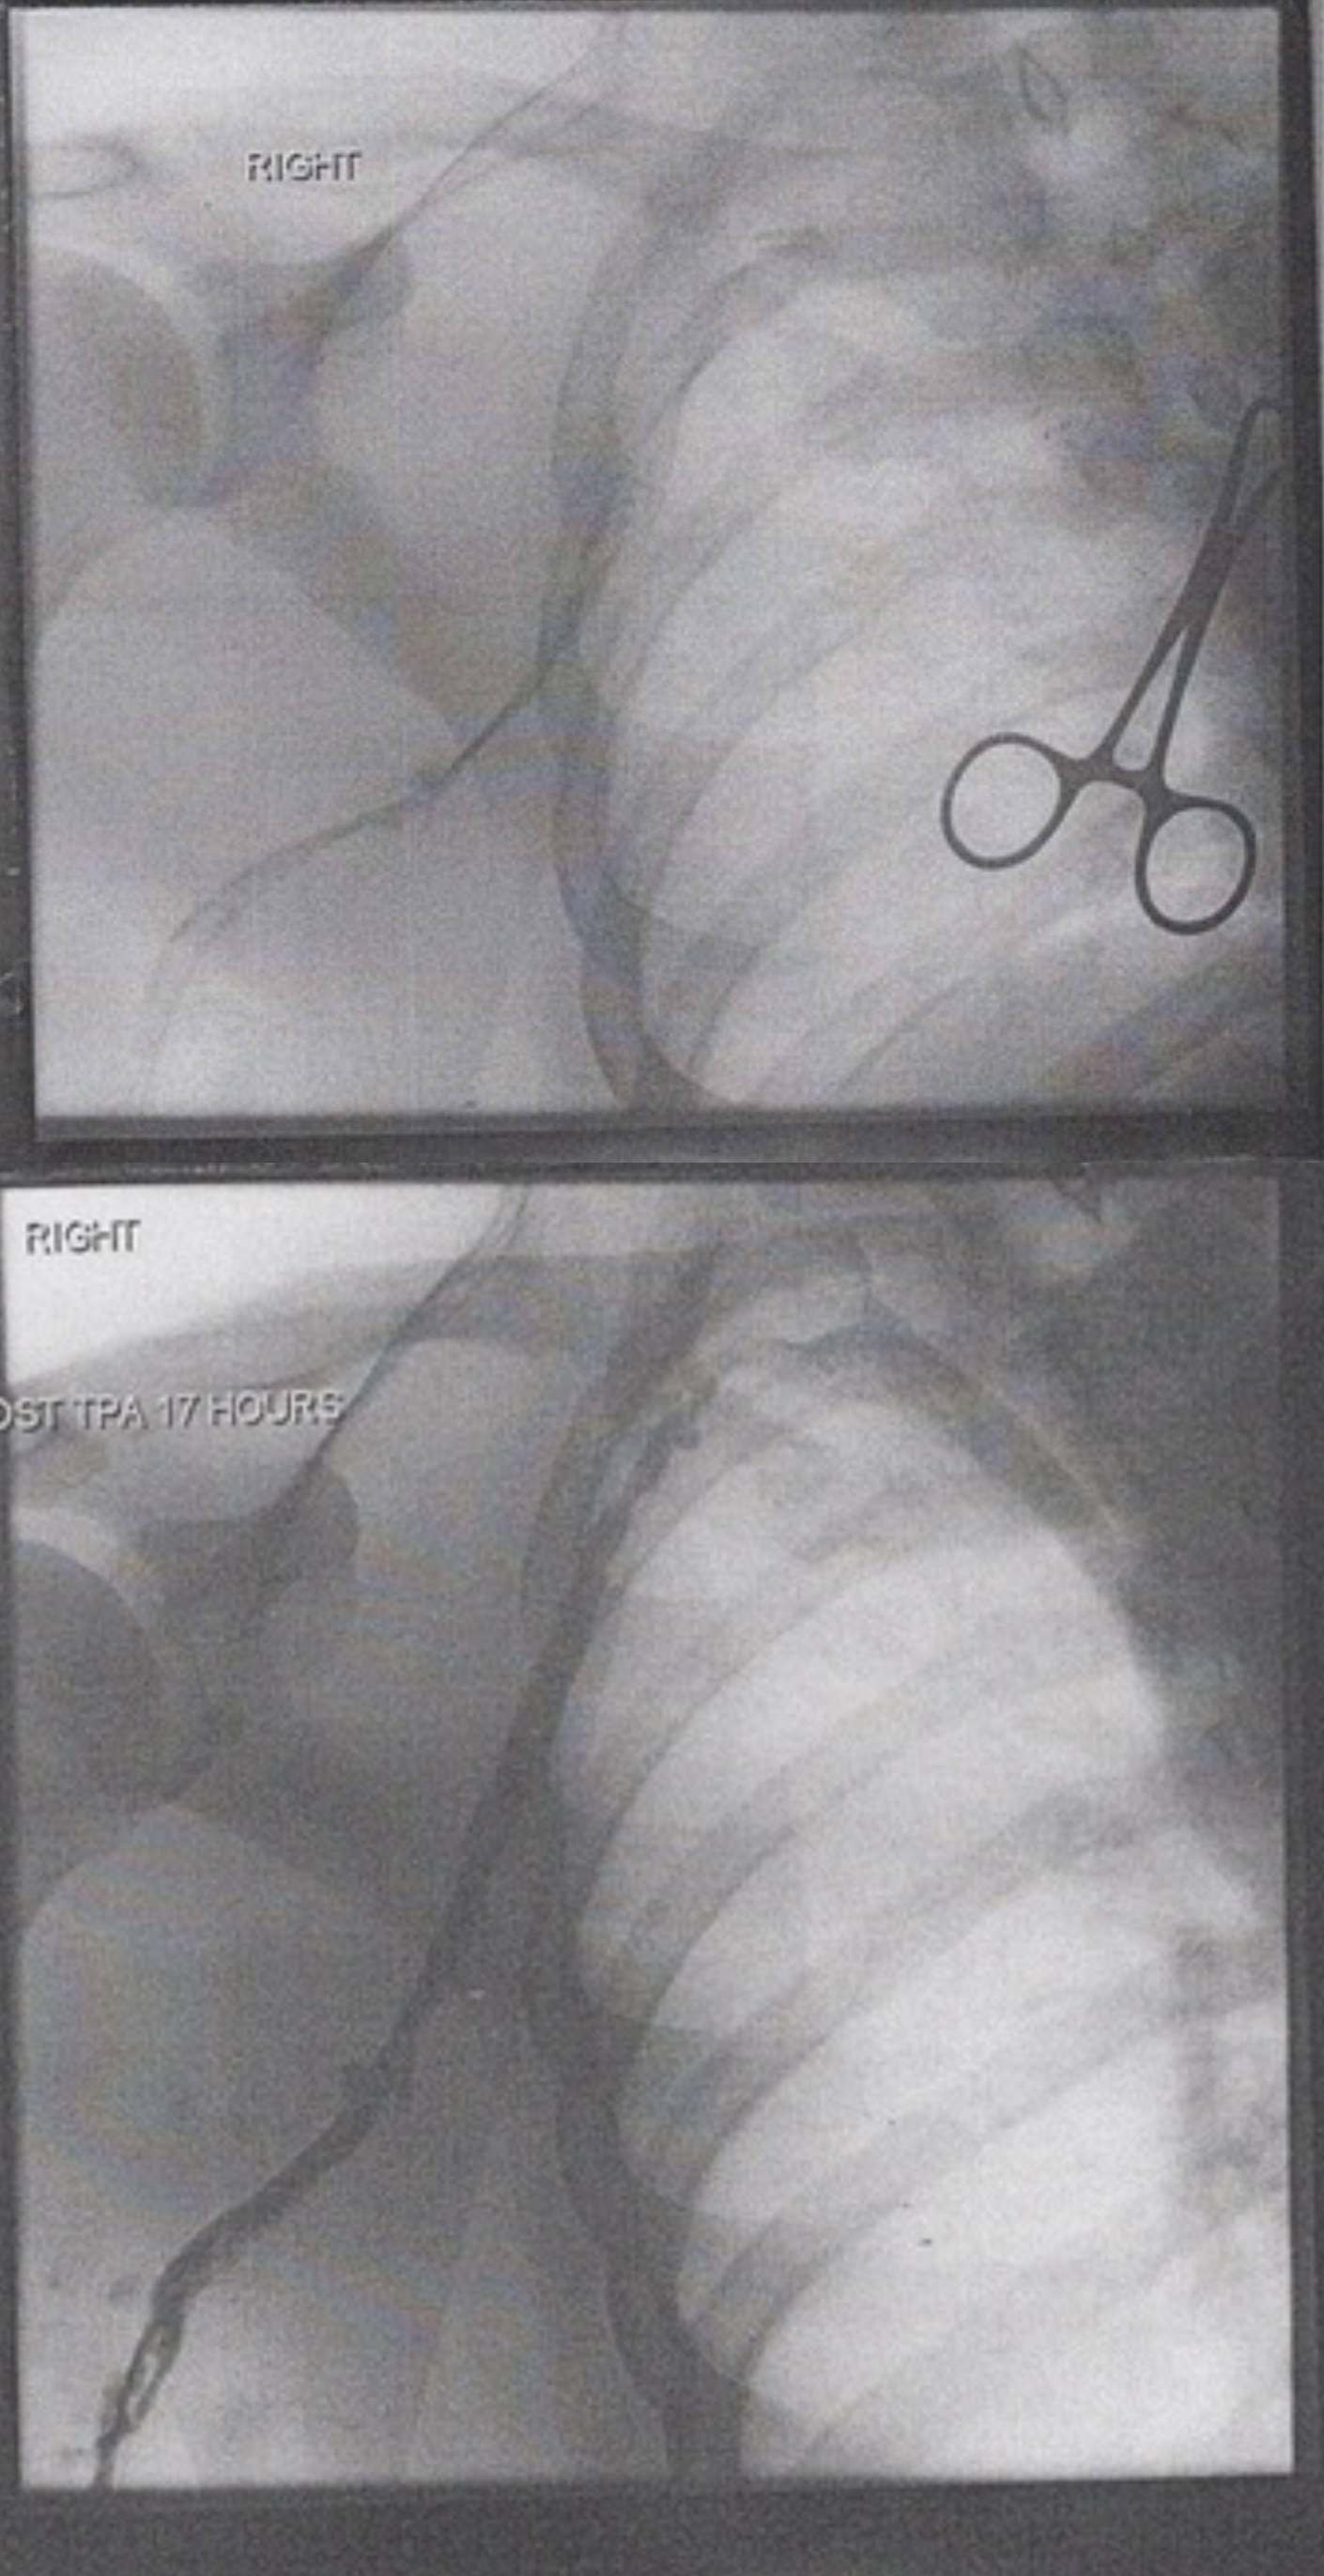

RIGHT: This label indicates the anatomical laterality of the image, confirming that the procedure is being performed on the patient’s right side. In the context of vascular imaging, establishing laterality is a critical safety step to ensure the correct limb or vessel is being treated.

POST TPA 17 HOURS: This annotation marks the timeline of the therapeutic intervention, indicating that the second image was captured 17 hours after the administration of Tissue Plasminogen Activator. It serves as a benchmark to evaluate the effectiveness of the chemical thrombolysis in dissolving the clot over this specific duration.

Venography, also known as phlebography, is an X-ray examination that uses an injection of contrast material to show how blood flows through the veins. While ultrasound is often the first line of defense for diagnosis, contrast venography is frequently used during interventional procedures. The images provided illustrate a classic “before and after” scenario involving a deep vein thrombosis (DVT), likely in the upper extremity (such as the subclavian or axillary vein). The top image reveals the severity of the blockage, while the bottom image highlights the restoration of blood flow.

The upper image demonstrates a critical interruption in venous return. In a healthy venogram, the contrast dye should fill the vessel lumen completely, appearing as a wide, smooth, dark ribbon on the X-ray. However, the pre-treatment image shows a “string sign” or faint collateral flow. This occurs when a thrombus (blood clot) occupies the majority of the vein’s interior. The clot is composed of aggregated platelets and a mesh of cross-linked fibrin. This obstruction increases hydrostatic pressure behind the clot, forcing blood to find alternative, smaller pathways (collaterals) to return to the heart, which is often visible as a network of thin, spider-web-like vessels.

The bottom image, labeled “Post TPA 17 Hours,” visually confirms the biochemical success of the treatment. Tissue Plasminogen Activator is a serine protease found on endothelial cells involved in the breakdown of blood clots (fibrinolysis). When administered therapeutically, usually via a catheter placed directly into the clot, it permeates the fibrin mesh. It cleaves the arginine-valine bond in plasminogen to form plasmin. This plasmin then digests the fibrin threads that hold the clot together, effectively liquefying the obstruction.

In the post-treatment venogram, the contrast dye now fills the vein widely and uniformly. The caliber of the vessel appears significantly larger than in the top image, not because the vein has grown, but because the lumen has been recanalized—the obstruction is gone, allowing the contrast to fill the entire space. This restoration of venous return immediately alleviates the back-pressure in the limb, reducing swelling and preventing the long-term sequelae of venous stasis. The clarity of the vessel walls in the second image suggests that the thrombus was relatively fresh, as older, chronic clots are often resistant to chemical lysis.